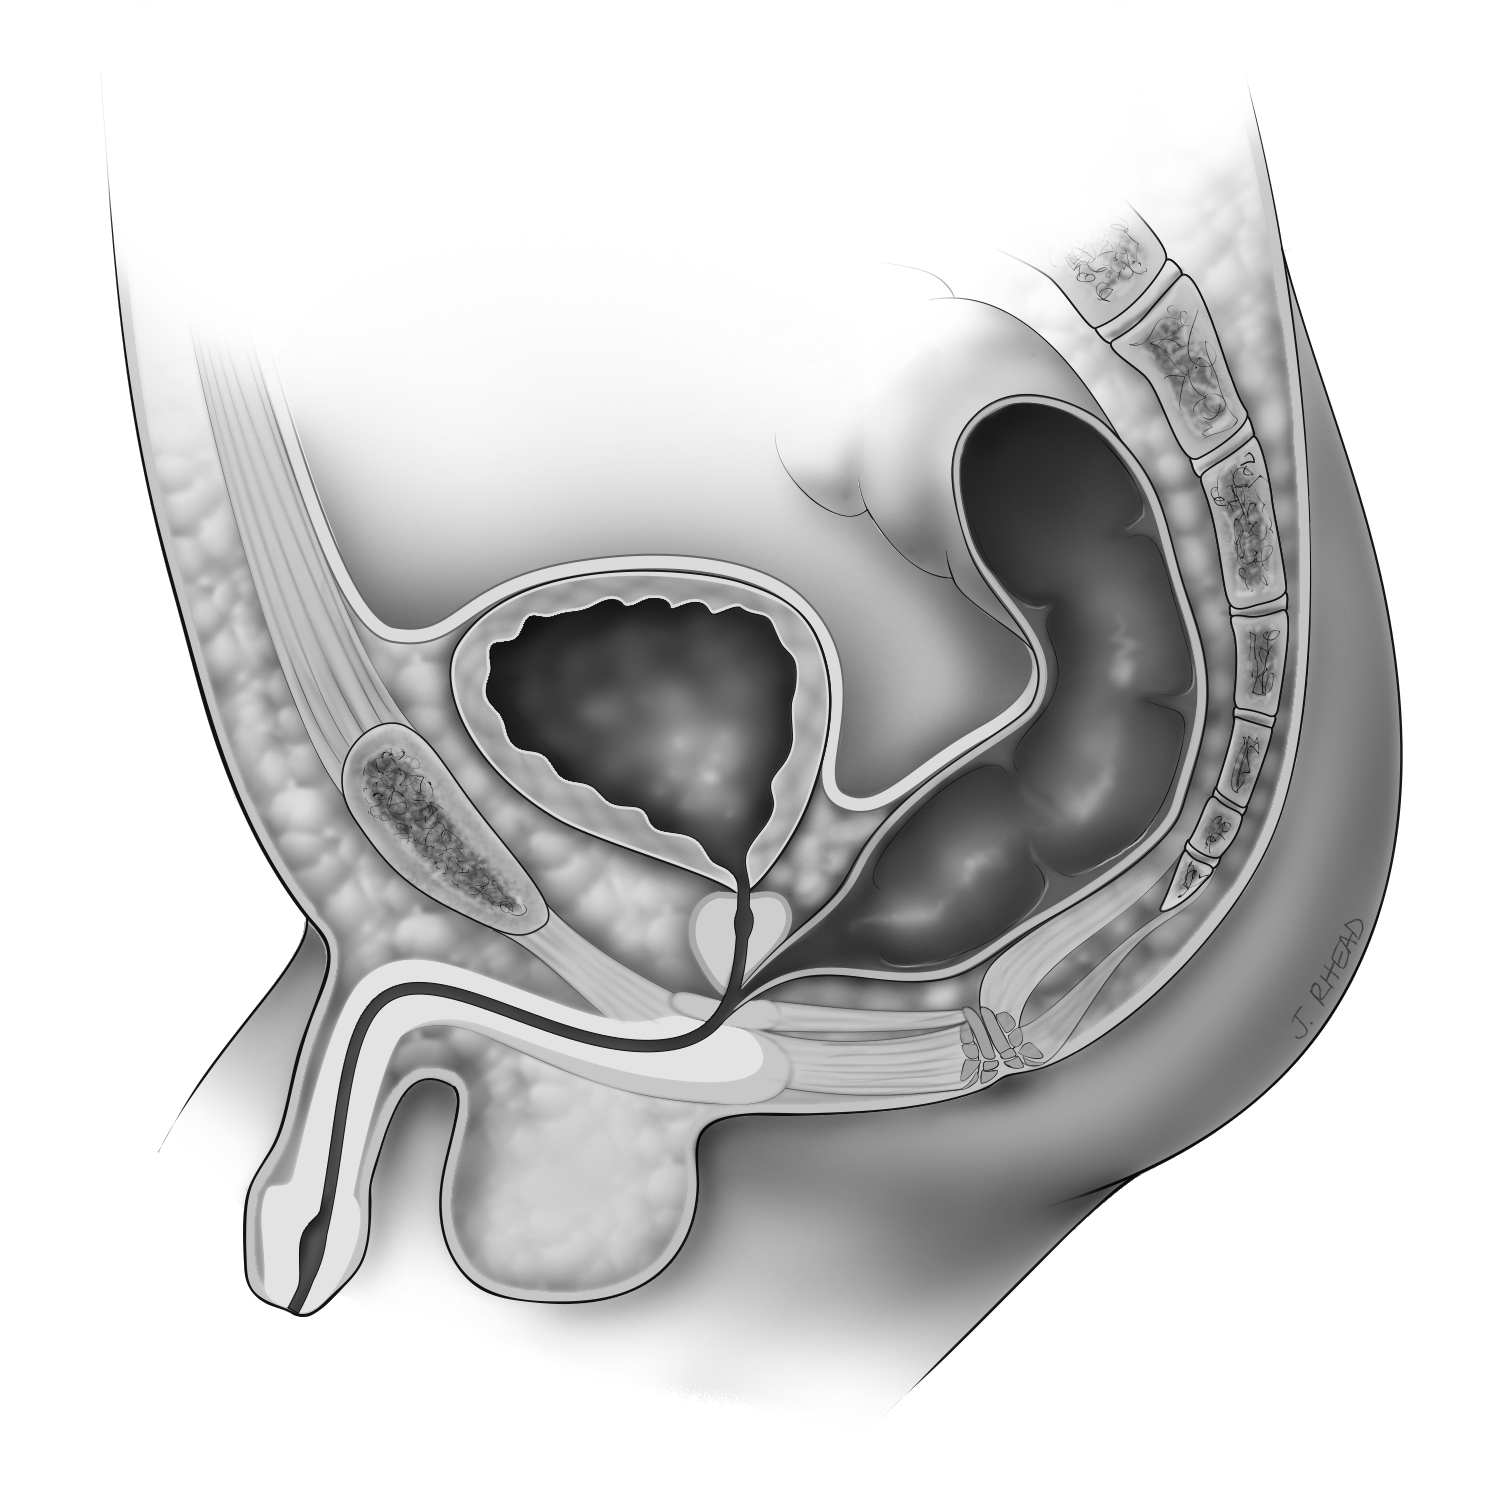

Imperforate Anus Without Fistula

The rectum ends in a blind pouch with no opening on the bottom